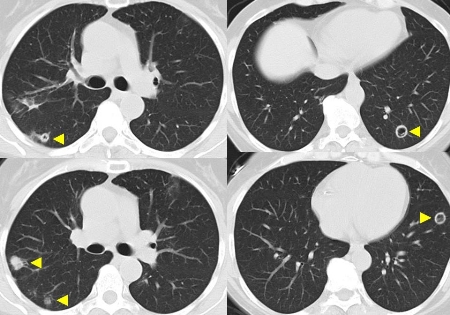

Granulomatose com poliangiite

Nódulos pulmonares cavitários na granulomatose com poliangiite (anteriormente conhecida como granulomatose de Wegener)

Do acervo do Dr. Eamonn Molloy, usado com permissão